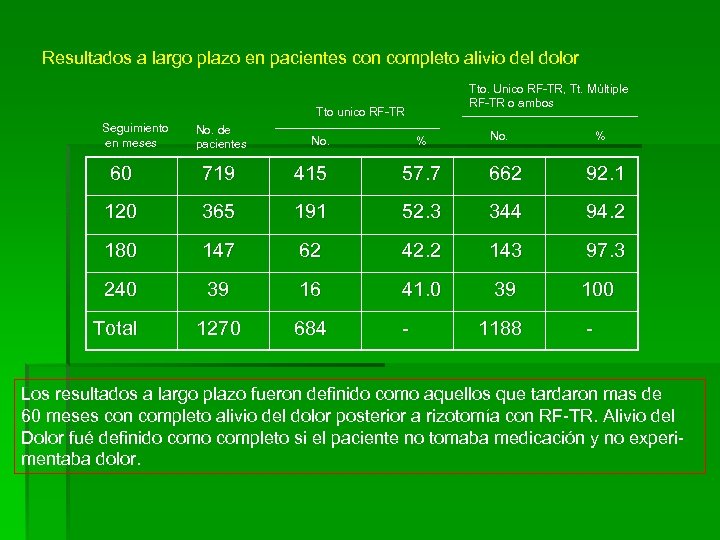

Resultados a largo plazo en pacientes con completo alivio del dolor Tto. Unico RF-TR, Tt. Múltiple RF-TR o ambos Tto unico RF-TR Seguimiento en meses No. de pacientes No. % 60 719 415 57. 7 662 92. 1 120 365 191 52. 3 344 94. 2 180 147 62 42. 2 143 97. 3 240 39 16 41. 0 39 100 Total 1270 684 - 1188 - Los resultados a largo plazo fueron definido como aquellos que tardaron mas de 60 meses con completo alivio del dolor posterior a rizotomía con RF-TR. Alivio del Dolor fué definido completo si el paciente no tomaba medicación y no experimentaba dolor.

Resultados a largo plazo en pacientes con completo alivio del dolor Tto. Unico RF-TR, Tt. Múltiple RF-TR o ambos Tto unico RF-TR Seguimiento en meses No. de pacientes No. % 60 719 415 57. 7 662 92. 1 120 365 191 52. 3 344 94. 2 180 147 62 42. 2 143 97. 3 240 39 16 41. 0 39 100 Total 1270 684 - 1188 - Los resultados a largo plazo fueron definido como aquellos que tardaron mas de 60 meses con completo alivio del dolor posterior a rizotomía con RF-TR. Alivio del Dolor fué definido completo si el paciente no tomaba medicación y no experimentaba dolor.